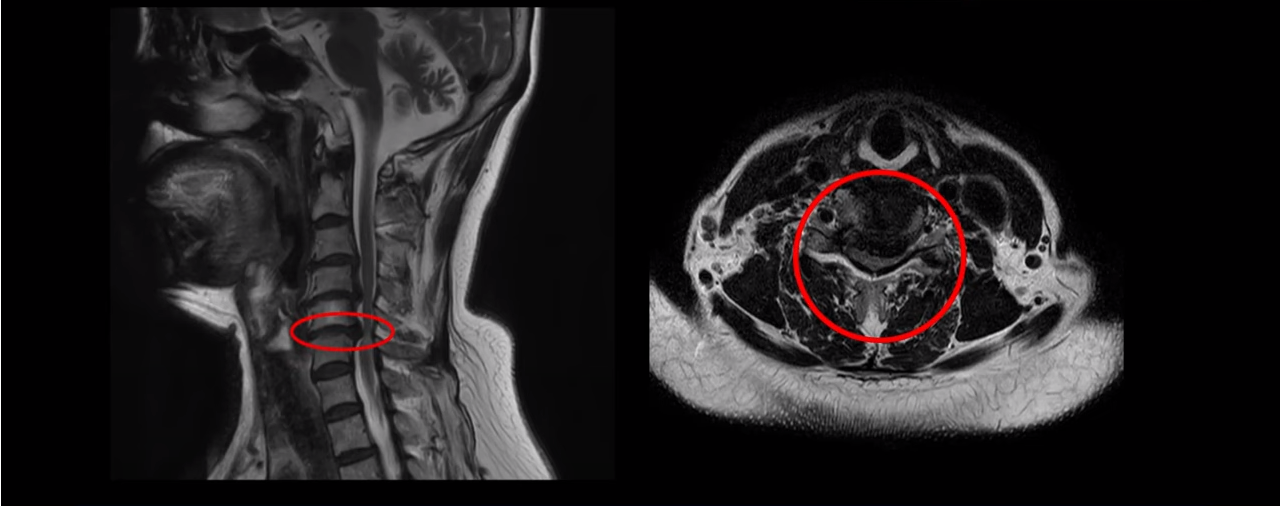

이 환자분은 목디스크 5, 6번에 심한 디스크로 인해 경추척수증이 발생한 환자입니다. 심하게 밀려 나온 디스크로 인해 척수신경이 눌려 신경손상이 하얗게 보입니다.

이 환자분의 증상은 양손바닥에 다 마비가 오고 다리에 힘이 빠지면서 균형을 못 잡고 비틀대면서 잘 걷지 못하는 상태였는데, 이는 전형적인 경추척수증의 증상이죠. 대학병원에서 별다른 자세한 설명 없이 무조건 수술해야 된다는 말에 저희 모커리한방병원에 내원하셨습니다.